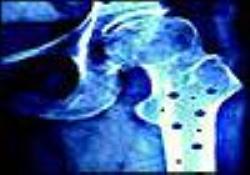

ترمیم بافت استخوانی بدون نیاز به عمل جراحی/ نتایج آزمایش‌ها بر روی نمونه حیوانی

محققان پژوهشگاه مواد و انرژی با استفاده از شیشه زیست فعال موادی را برای ترمیم بافت استخوانی عرضه کردند و امیدوارند با نهایی شدن آزمایش‌ها در آینده بدون نیاز به عمل جراحی اقدام به ترمیم بخش‌های آسیب دیده استخوانی کنند.دکتر نادر نظافتی- یکی از محققان این پروژه در گفتگو با خبرنگار مهر، مواد اصلی نانوکامپوزیت تولید شده را شیشه زیست فعال دانست و گفت: این مواد قادر هستند که در بافت نرم و سخت بدن چسبندگی ایجاد کنند.

وی با بیان اینکه نانو کامپوزیت تولید شده تزریق پذیر است، اظهار داشت: این نانو کامپوزیت برای ترمیم نواحی تومورهای استخوانی و درمان بیماری‌های عفونی استخوان استفاده می‌شود و قادر است بدون نیاز به عمل جراحی اقدام به ترمیم بخش‌های آسیب دیده استخوان کند.

نظافتی، با اشاره به عملکرد این مواد، خاطر نشان کرد: نانو کامپوزیت تولید شده حاوی ترکیبات پلی ساکارید مانند سدیم آلژینات زیست تخریب پذیر است از این رو زمانی که این مواد در میان مهره‌های آسیب دیده تزریق می‌شود با ترمیم بخش آسیب دیده به تدریج بافت استخوانی جایگزین کامپوزیت تزریق شده می‌شود.

عضو هیات علمی پژوهشگاه مواد و انرژی، با بیان اینکه با استفاده از این روش بیماری‌های استخوانی بدون نیاز به عمل جراحی درمان می‌شود، اضافه کرد: برای درمان ساختارهای پیچیده استخوانی از سیمان استخوانی کلسیم فسفاتی استفاده می‌شود که با استفاده از این روش نیازی به انجام اعمال جراحی نخواهد بود.